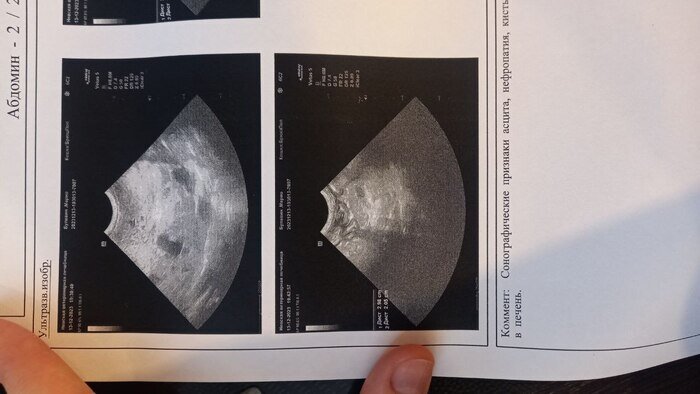

Добрый времени суток Нужна консультация ветонколога Коту (6 лет) диагностировали рак печени. Печень сильно увеличена, как сказал врач на снимках чёрные пятна это метостазы, но кот себя чувствует хорошо, ест и пьёт как обычно, с туалетом проблем нет, в поведении и состоянии отклонений нет, единственное что было это когда он долго лежит, потом встаёт и его штормит, как будто пьяный, такое было замечено пару раз. Если тут есть врач, который сможет мне дать хоть какую-то информацию по снимкам или что лучше дальше делать, буду очень признателен. Анализы крови не делали, врач сказал, что это 100% рак